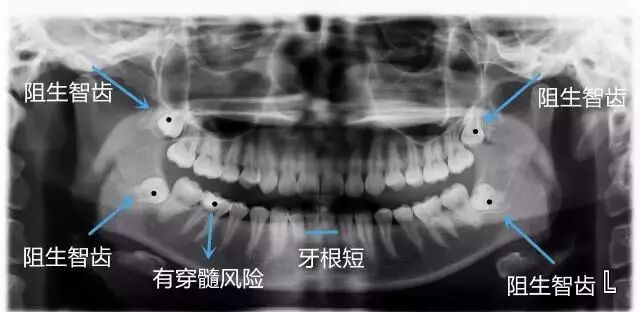

嘴凸分两种,一种叫牙性嘴凸,另一种叫骨性嘴凸。

简单来讲,牙性嘴凸是牙齿问题导致的嘴凸,而骨性嘴凸是由骨头问题造成的。

牙性嘴凸只要正畸就能轻松搞定,而骨性嘴凸则需要正畸-正颌联合治疗,比较麻烦,而且很贵。